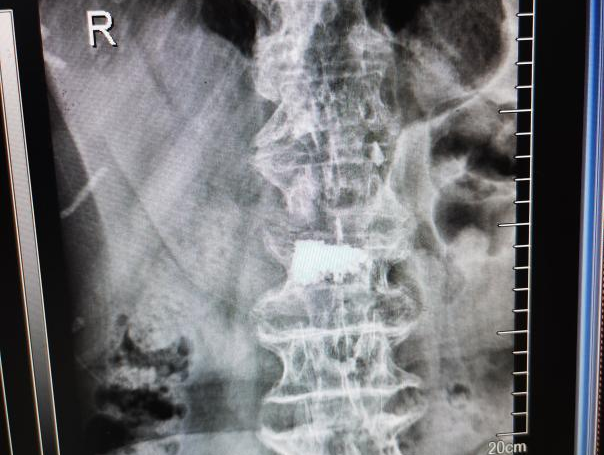

多年来,贵州航天医院各科室紧跟医学前沿,不断强技术、补短板,大力开展新技术、新项目,完成了许多高精尖、高难度、本地区“首例”的技术,填补了医院医疗技术空白,满足了群众日益增长的医疗需求。 贵州航天医院骨科率先在遵义地区开展骨搬移技术,截至目前,已治愈慢性骨髓炎、感染性骨不连、骨缺损、脉管炎、糖尿病足患者200余例,糖尿病足治疗保肢率达到98%。 本期,我们将为大家带来骨科特色技术——骨搬移技术(Ilizarov)。 案例分享 一名59岁的患者,身患糖尿病12年,在来我院3个月前出现了右脚溃烂的症状,来院就诊时,患者的右脚十分红肿,右脚脚趾坏死,伤口处不断流出黑红色脓液,情况十分严重。在接诊到患者时,骨科专家团队高度重视,立刻为患者完善了CT血管造影(CTA)等相关检查,诊断为:2型糖尿病,糖尿病周围血管病变,右糖尿病足。 术 前 考虑到患者情况比较严重,为最大限度保证患者肢体完整,科室专家团队进行了严格的讨论评估,为患者制定了骨搬移技术治疗方案,在征得患者及其家属的同意后,成功通过搬移骨块为患者进行治疗,促进患者病变肢体血管再生。 胫骨横向骨搬移外架固定 清除感染病灶 术后调节外架,通过搬移骨块 促进患肢血管再生 患者在术后三周前来换药,观察到感染得到进一步控制;术后六周复查,患者病变处已愈合,进行CT血管造影(CTA)后可明显观察到足部血管再生。 术后3周 术后6周愈合 CT血管造影见足部血管再生 糖尿病患者全身与局部的问题互为影响,形成恶性循环,糖尿病足溃疡创面迁延不愈,常见干性坏疽、湿性坏疽、趾坏死、深且大的溃疡以及骨髓炎等症状,还可导致脓毒血症,以往为保全生命,患者被迫选择一次或多次截肢。骨搬移技术的发展进步,能在血糖有效控制、局部有效清创下,有效促进患肢微血管再生,改善患肢血供,达到糖尿病足更快治疗康复的目的,并能根据病变情况最大限度的保障患者肢体完整。 什么是骨搬移技术 骨搬移技术是通过使用专用的骨外固定器固定骨段,每天缓慢牵拉,在牵拉搬移过程中,骨段尾部形成新骨及新的软组织,从而修复骨骼缺损及软组织缺损。是治疗大段骨缺损、骨不连、骨感染、肢体畸形的金标准方法,也用于治疗脉管炎、糖尿病足等肢体缺血性疾病。 骨感染缺损 切除感染段 搬移骨段 新骨形成 骨感染根治愈合 骨搬移技术原理 生物组织在持续、稳定、缓慢牵拉下,能刺激细胞分裂、组织再生,骨外固定技术运用该原理,通过持续缓慢调节外固定器形成牵拉张力,促进牵引成骨与相邻组织再生,如神经、血管、肌肉、皮肤等再生,达到治疗大段骨缺损、肢体缺血如糖尿病足等疾病的目的。 骨搬移技术优势 (一)除治疗骨缺损、骨不连外,有更广的适用范围,利用组织再生、血管再生等特性,能大量运用于肢体畸形的矫形、糖尿病足等的治疗。 (二)治疗效果确切,重建肢体外型和功能,极大降低截肢率和残疾率。 (三)明显提高了患者生活质量,极大减轻其家庭及社会负担。 肢体畸形的矫形 慢性骨髓炎 骨段切除 术后1年 濒临截肢的脉管炎术后6周 难愈创面术后3周 贵州航天医院骨科 专家团队 赵学平 骨科主任 主任医师 临床擅长:从事骨科临床工作30余年,对骨科常见疾病的诊治具有丰富的临床经验。 世界中医药联合会脊柱康复专业委员会常务理事,中华中医药学会整脊分会常务委员,中国中西医结合学会骨伤科分会肢体矫形功能重建与康复专家委员会常务委员,中国研究性医院学会骨科创新与转换专业委员会关节外科学组保髋工作委员会常委,中国康复技术转化及发展促进会骨外科与康复技术转化专业委员会常务委员,泛珠三角区域运动医学联盟(PPRD-SMA)理事会常务理事,中国研究型医院学会运动医学专业委员会委员,贵州省中医药学会整脊分会副主任委员,贵州省中西医结合学会银质针专业委员会副主任委员,贵州省康复医学会骨与关节专业委员会常务委员,贵州省人民医院骨科专科联盟常务理事,贵州省康复医学会骨内科专业委员会常务委员,中华医学会贵州省骨科学会委员,贵州省康复医学会脊柱脊髓专业委员会常务委员,贵州省运动医学分会委员,贵州省康复医学会骨与软组织肿瘤专业委员会委员,遵义市医学会创伤分会副主任委员,贵州省康复医学会骨内科专业委员会遵义地区分会常务委员,遵义市医疗事故鉴定、伤残鉴定、工伤鉴定、司法鉴定专家。 长期从事骨科临床研究及教学工作,在国家级、省部级杂志发表论文20余篇,SCI论文2篇,参与主编骨科专著2部,主持省部级科研项目2项,参与指导省部级、市级科研项目6项。 陈明勇 骨科副主任 副主任医师 临床擅长:从事创伤骨科工作约20年,对骨缺损、骨不连、骨肿瘤、肢体畸形等的肢体矫形重建及功能重建,慢性化脓性骨髓炎的根治治疗、糖尿病足的保肢治疗、快速康复理念(ERAS)下的老年骨折的诊治,四肢复杂骨折的诊治,四肢骨折等微创手术治疗具有丰富的临床经验。 2004年毕业于遵义医学院临床专业,曾在中国人民解放军总医院、广西医科大学第一附属医院、上海第六人民医院骨科进修。中国中西医结合学会骨伤科专业委员会横向骨搬移治疗糖尿病足及微血管网再生学组首届委员,遵义市医学会创伤分会常务委员。 瞿 辉 骨科 副主任医师 临床擅长:对骨科的常见病、关节外科、脊柱外科及运动医学疾病的诊治具有丰富的临床经验,熟练掌握骨科手术操作技术。 毕业于遵义医学院临床医学系,2005年前往广州中山大学第一附院骨显微医学部进修学习,2011年前往成都华西医院进修学习,并多次在省内外学习骨科相关知识,是中华医学会骨科分会会员。 赵兴东 骨科 主任医师 临床擅长:擅长骨科的常见病及各种创伤、四肢骨折创伤修复、骨感染、手足疾病的诊治和手足体表畸形的矫形整复,熟练掌握骨科四肢骨病及创伤的手术操作技术,尤其在四肢关节复杂性损伤、手足外伤、组织缺损创面、难治创面的皮瓣修复方面及平足、高弓足矫形方面及四肢慢性疼痛诊治、康复方面具有丰富的临床经验。 硕士研究生,毕业于遵义医学院临床外科系,2015年前往山东省立医院手足外科进修学习;遵义市医学分会创伤分会第一、二届委员,遵义市手外科医学会第二委届员会常务委员;在省级及省级以上期刊发表文章9篇,参编著作2部,参与主持并完成市级课题1项,参与市级课题2项、省级课题1项。 张俊凯 骨科 副主任医师 临床擅长:从事骨科临床工作28年,对创伤骨折、骨感染、骨缺损、骨不连等外科诊治,四肢骨折的微创手术治疗,四肢复杂骨折(如关节内粉碎性骨折、多发骨折等)的损伤控制及手术治疗等具有丰富的临床经验。 1995年毕业于遵义医学院临床专业,2009年前往复旦大学附属医院骨科进修1年。 卢懿明 骨科 副主任医师 临床擅长:从事骨科工作18年,对创伤骨折、四肢骨折的微创手术治疗、四肢复杂骨折(如关节内粉碎性骨折、多发骨折等)的损伤控制及手术治疗,尤其是髋部骨折的PFNA等微创技术,踝关节骨折、膝关节周围骨折的Mipo微创技术等具有丰富的临床经验,开展了4项新技术,发明6项新型专利技术。 2005年毕业于遵义医学院临床专业,2017年,前往南方医科大学第三附属医院骨科进修半年,回院后运用Mipo技术对骨干骨折及干骺端骨折的治疗技术,同时积极开展骨盆骨折、髋臼骨折腹直肌外侧切口的应用;发表了多篇专业论文,经常参与省内外学术交流会授课,获得医院荣誉称号多个。 邬夏荣 骨科 副主任医师 临床擅长:从事骨科工作16年,对四肢复杂骨折、骨肿瘤的诊治,尤其是足踝创伤、慢性踝关节损伤、平足症等诊疗具有丰富的临床经验。 2006年毕业于遵义医科大学临床医学专业,曾在陆军军医大学西南医院进修学习,发表多篇骨科学术论文。 余德怀 骨科 副主任医师 临床擅长:从事骨科工作10余年,对运动医学、骨关节、脊柱外科常见病、多发病的诊治具有丰富的临床经验。 硕士研究生,2011年毕业于遵义医学院临床医学专业,曾前往遵义医科大学附属医院运动医学专业进修学习;是贵州省医学会运动医学分会青年委员,西部关节镜联盟委员;发表多篇骨科学术论文。 冯 乾 骨科 副主任医师 临床擅长:从事骨科工作近20年,熟练掌握骨科多发病及常见病的诊治,尤其对脊柱退变性疾病的诊断及治疗具有丰富的临床经验,主要研究脊柱微创相关治疗方式,能熟练开展椎间孔镜及VBE。 曾前往北京大学第三医院进修学习疼痛及椎间孔镜、首都医科大学友谊医院专业进修脊柱内镜;是贵州省康复医学会第三届脊柱脊髓专业委员会委员;发明专利3项、发表脊柱外科专业论文多篇。 张艳金 骨科 副主任医师 临床擅长:从事骨外科工作16年,对复合伤、多发伤的救治、四肢骨干骨折、关节周围骨折、骨肿瘤、骨髓炎等诊治具有丰富的临床经验。 中共党员,硕士研究生,2006年本科毕业于山西医科大学第二临床医学院,2011年研究生毕业于北京军区总医院;在“老年COPD患者合并髋部骨折的诊治”国际合作课题组研究两年,在老年髋部骨折的诊治方面具有丰富的经验,并发表论文6篇;承担遵义市级课题1项;承担遵义医科大学的临床教学工作,获得遵义医科大学优秀带教老师荣誉。编撰有《骨科疾病诊疗精粹》一书,开展2项新技术,编撰地方规范《务川自治县创伤骨科常见疾病诊疗规范》一书。 赵小锋 骨科 副主任医师 临床擅长:从事骨科临床工作11年,对骨科常见病、多发病诊疗有较为丰富的临床经验,擅长脊柱相关疾病诊断及治疗,尤其是颈、腰、腿疼痛疾病诊断及治疗,擅长胸腰椎骨折微创经皮穿刺内固定术、经皮穿刺椎体成形术、经皮穿刺脊柱内镜下腰椎间盘摘除术、单纯开创腰椎间盘摘除术、腰椎滑脱复位椎间植骨椎融合内固定术、腰椎管狭窄减压融合内固定术及人工髋、膝关节置换术等。 2012年毕业于遵义医学院外科学专业硕士研究生,2019年参加“遵义市115医学人才精英计划”于上海交通大学第一附属医院培训学习,2023年于北京大学第三人民医院脊柱外科进修学习,曾获得遵义市优秀医师荣誉称号。 遵义市手外科第一届委员,遵义市医学会创伤分会第一届委员,遵义市医学会创伤分会第二届委员,贵州省康复医学会第三届脊柱脊髓专业会委员,遵义市医学会烧伤与整形外科学分会委员,发表论文5篇,其中国家级核心期刊1篇,SCI论文1篇,主持市级课题1项并结题,参与市级课题2项。 贵州航天医院骨科简介 基本情况 贵州航天医院(原3417医院)骨科组建于1968年,前身是以创伤和断肢(断指)再植闻名于世的上海市第六人民医院骨科,中国断肢(断指)再植的奠基者、中科院院士陈仲伟等著名专家、学者多次莅临科室指导医疗、教,是贵州省最早拥有专业骨科技术科室之一,在70年代开展了贵州省首例断肢(断指)再植手术。组建50余年来,诊治患者已逾百万,挽救了无数的伤病员,成为了保障遵义地区人民群众健康的重要支撑。 经过几代人的不懈努力,今天的骨科,已由创伤骨科发展至骨病、骨肿瘤、骨结核等领域,现有脊柱外科、关节外科、四肢创伤、手足外科四个亚专科,成为了集医疗、教学、科研于一体的综合学科,是贵州省临床重点专科、遵义市临床重点专科、遵义市骨科临床医学中心、遵义市基层骨科专科联盟理事长单位。 科室目前开放床位110张,共有医护人员50余人,副高级以上专家18人,硕士研究生15人。拥有一流骨科医疗设备多台,每年不定期选派优秀技术骨干到全国各大知名医学院校进修、学习、参观、交流,并邀请国内、国外知名专家教授来院进行交流、指导,通过不断引进国内外先进的诊疗技术,科室医疗技术水平稳步提升,为广大人民群众提供了优质的医疗服务。 专科特色 骨一科 (一)骨缺损、骨不连的肢体与功能重建 胫骨横向骨搬移技术治疗糖尿病足: (二)慢性骨髓炎的根治治疗 (三)肢体缺血性疾病如糖尿病足、脉管炎的保肢治疗 (四)皮瓣修复 (五)复杂创伤的治疗 (六)老年髋部骨折及小儿骨折快速手术 老年髋部骨折: 骨二科 (一)胸腰椎骨折微创经皮椎弓根螺钉固定术 (二)老年性骨质疏松性患者腰椎滑脱脊柱内固定术(骨水泥螺钉) (三)V形双通道脊柱内镜技术(VBE)腰椎融合术治疗腰椎退行性疾病 (四)老年性骨质疏松性骨折(PVP/PKP)术 (五)人工髋关节置换术 (六)双侧股骨头坏死人工全髋关节置换 (七)右侧全髋置换术后假体周围骨折翻修 (八)人工膝关节置换术 (九)人工膝关节假体松动翻修 (十)关节镜技术 传统手术切口 关节镜技术切口 诊疗范围 骨一科 1.四肢创伤、矫形。 2.手、足踝外科。 骨二科